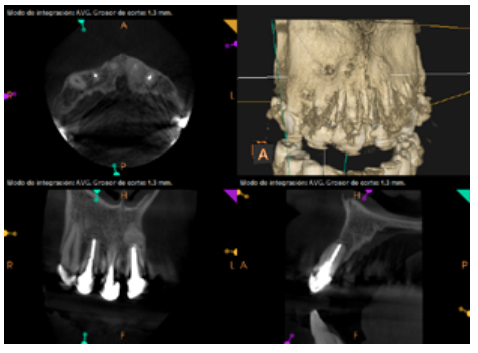

To confirm the endodontic origin and the size of the lesions, tomographic examinations were performed with a slice thickness of 75 microns using CBCT CS8100 (Carestream Dental™), in which radiolucent periapical lesions were observed at the level of 12, 11, 21 (with bicortical involvement), 25 and vestibular roots at 26 (Figures 4 to 8).

After the microsurgery was performed on 25, the patient had no symptoms and the control tomographies at 12 months (in 25) and at 18 months in the remaining teeth showed regeneration of pre-existing radiolucent periapical lesions on all treated teeth (Figures 13 to 16).

Radiological checks were carried out at 6, 12 and 18 months using CBCT, which showed the absence of symptoms and a reversal of the chronic infection, as well as progressivity and stability in apical bone regeneration. At the level of 21, periapical radiopacity was observed, without loss of volume, and an absence of invasion of the space preserved by the surrounding soft tissue. Although some authors have used plasma rich in growth factors (PRGF) associated with Bio-Oss™ and Bio-Gide™ in cases similar to ours, we obtained adequate results without using PRGF as an additional technique13.